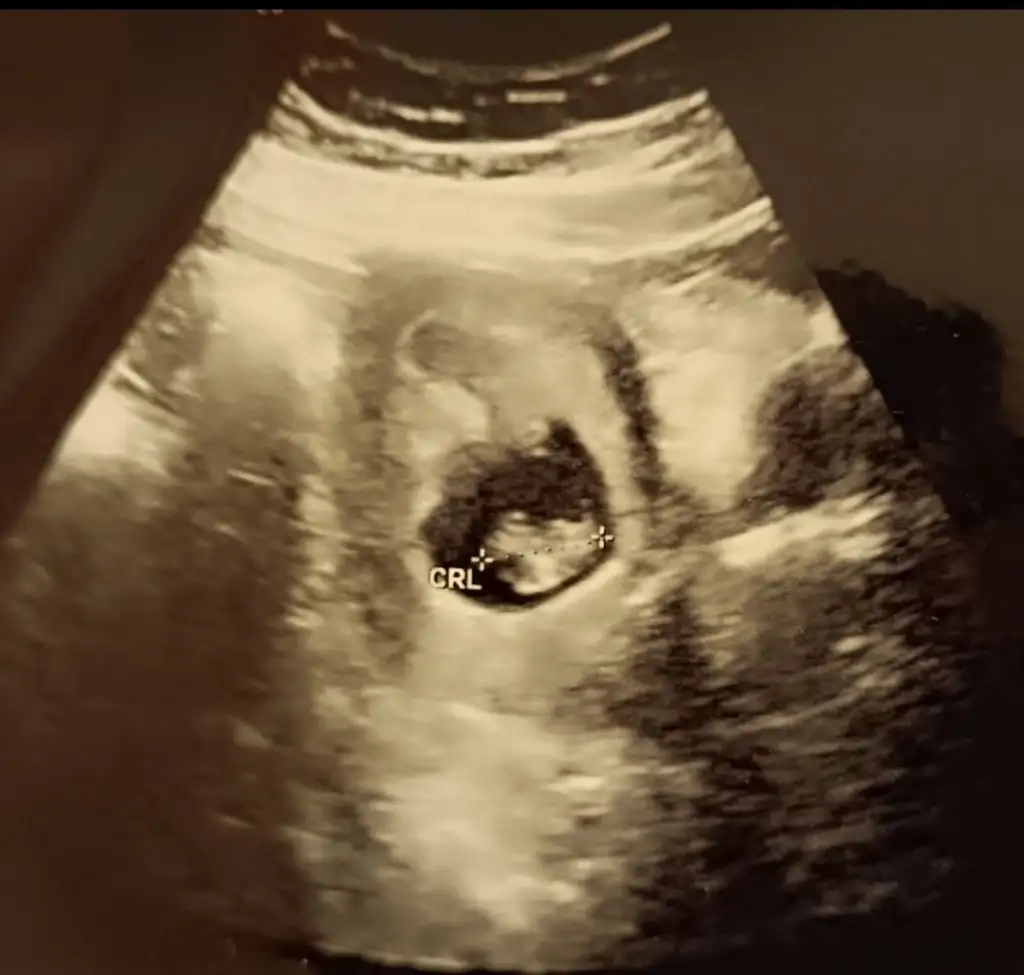

Ben plasantasına bakıyorum bır teorıye gore kese seklınden degılNasıl anlıyorsunuz peki bakalım doğru çıkacak mı iki prensesim var bakalım hayırlısı

Bende sekline bakiyorumBen plasantasına bakıyorum bır teorıye gore kese seklınden degılnasip eder Rabbım inşallah

Sanki kiz gibi canim ya pekde emin olamadim

O zaman ikinizde kız dedinizSanki kiz gibi canim ya pekde emin olamadim![]()

Yapısı erkek gibi sanki yaaaa![]()